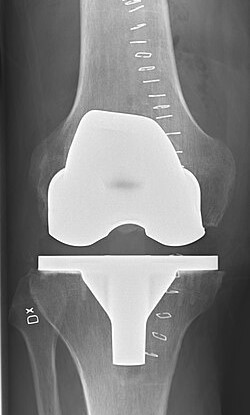

Joint replacement is a highly effective surgical procedure designed to relieve pain and restore mobility in patients suffering from severe joint damage. When joints such as the hip or knee become worn out due to arthritis, injury, or aging, everyday activities like walking, climbing stairs, or even standing can become difficult. Joint replacement surgery replaces the damaged parts of the joint with artificial implants, allowing patients to regain comfort and function in their daily lives.